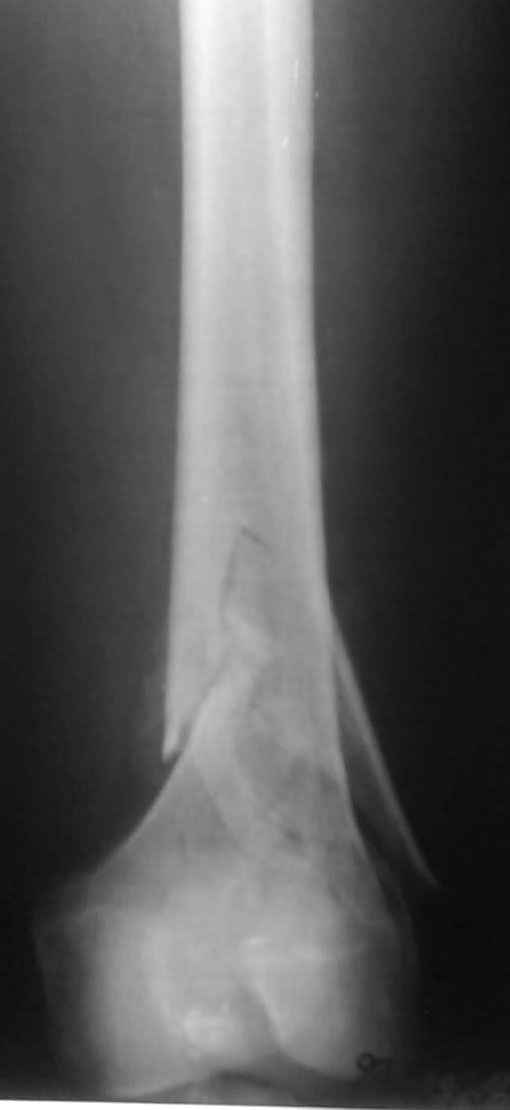

Привет из Нижнего Новгорода! К нам поступил пациент 25 лет с закрытыми переломами обеих бедренных костей, прошел месяц после травмы. Слева - внутрисуставной перелом, поэтому выбор здесь очевиден, открытая репозиция, стабильная фиксация, скорее всего LCP DF, а справа - мнения учёных, как говорится, разошлись. Лично я, как лечащий врач, за закрытый интрамедуллярный остеосинтез DFN. Со мной согласна половина коллектива, другая - за интрамедуллярный остеосинтез (DFN,UFN) но с открытой реопозицией, поскольку при закрытой методике все осколки останутся где-то сбоку, получится дефект и вдруг не срастется!Философский вопрос: что лучше - красивая рентгенограмма или сохранение кровоснабжения? Очень важно мнение коллег! Смирнов Алексей

Приветствую всех коллег!!Во первых слева хотелось бы видеть четкую боковую проекцию а лучше КТ. По р-мам есть сомнения насчет повреждения суставной поверхности. При подобных переломах даже внутрисуставных без смещения хорошие результаты показал закрытый ретроградный остеосинтез универсальным бедренным стержнем Деост.Кстати при внутрисуставном переломе возможно применение вместо винтов стягивающих болтов!!(См. метод.Деост).При переломе справа также стержень Деост. Однако без открытия Вам не удастся устранить интерпозицию, только промучаетесь!Из минимального разреза удалите интерпозициб и фиксируйте стержнем. Причем универсальный стежень Деост позволяет фиксировать дистально минимум на трех уровнях!